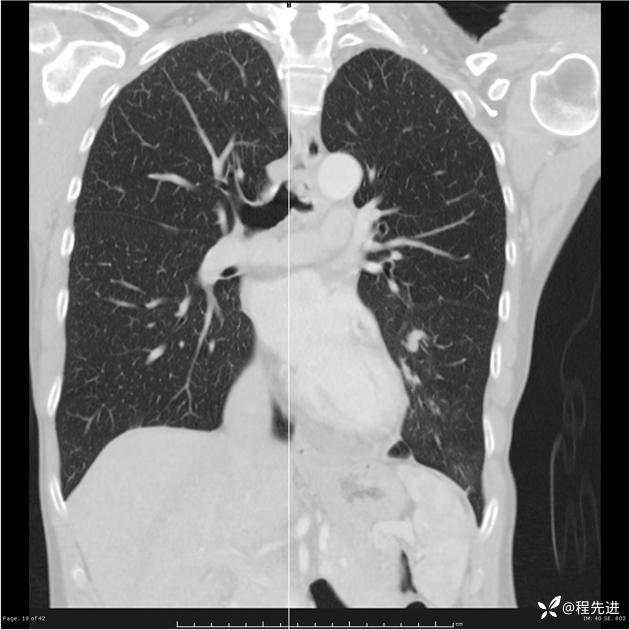

病例女,53岁,气管、左主支气管、下叶支气管内结节,乳头状瘤?期待你的精彩解读

女,53岁

乳头状瘤?